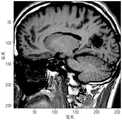

Thus, an imaging modality such as Magnetic Resonance Imaging (MRI) may be used in conjunction with ultrasound focusing during non-invasive treatment to monitor the target tissue and the location of the ultrasound focus. In general, theMRI system 100 as shown in fig. 1 includes a staticmagnetic field magnet 102, one or moregradient field coils 104, a Radio Frequency (RF)transmitter 106, and an RF receiver (not shown). (in some embodiments, the same device may be used alternately as a radio frequency transmitter or a radio frequency receiver.) the magnet includes aregion 108 that receives apatient 110 and is used to provide a static, relatively uniform magnetic field over the patient. The time-varying magnetic field gradients generated by thegradient field coils 104 overlap the static magnetic field. TheRF transmitter 106 is used to transmit a sequence of RF pulses to thepatient 110 to cause the patient's tissue to transmit a (time-varying) RF response signal that is integrated over the entire (two-or three-dimensional) imaging region and sampled by the RF receiver to generate a time sequence of response signals that constitute the raw image data. These raw data are transmitted to thecalculation unit 112. Each data point in the time series can be understood as a fourier transform value of the local magnetization in relation to the position at a particular point in K-space (i.e. the wave vector space), where the wave vector K is a function of the development of the gradient field over time. Thus, by performing an inverse fourier transform on the time series of response signals, thecalculation unit 112 may reconstruct a real-space image of the tissue using the raw data (i.e. an image showing the measured tissue properties affected by magnetization as a function of spatial coordinates). Then, a real-space Magnetic Resonance (MR) image is displayed to the user. TheMRI system 100 may be used to plan a medical procedure and monitor the progress of treatment during the procedure. For example, MRI may be used to image an anatomical region, locate target tissue (e.g., a tumor) within the region, direct conduction of a beam generated by theultrasound transducer 114 to the target tissue, and/or monitor temperature within and around the target tissue.

FIG. 1 illustrates an MRI guided focused ultrasound system according to various embodiments of the present invention;

FIG. 4 is an exemplary image of a treatment region depicting patient tissue targeted for treatment according to various embodiments of the present invention;

Figure 4 is an MRI real space image of a human patient prior to treatment with focused ultrasound energy. The image in fig. 4 depicts a cross-sectional slice of the brain of a patient. Figure 5 is a temperature map constructed from an acquired MRI scan after heating a target within a patient's body with focused ultrasound energy. As shown, the temperature rise is limited to a small portion of the treatment area, approximately elliptical. The temperature increase at the center of the target was about 30 deg.c and the temperature increase decreased radially from the center of the target. Fig. 6 is a K-space diagram corresponding to the temperature change presented by the temperature diagram of fig. 5. Fig. 6 graphically illustrates normalized values for relative changes between the K-space representation of fig. 4 after treatment (i.e., the thermal model of fig. 5 applied to the image in fig. 4) and the baseline K-space representation acquired from fig. 4 before treatment. The upper limit of the relative variation shown in fig. 6 is 30% of the complex K spatial variation. As shown in fig. 6, the region of greatest variation falls approximately within the 110-140 rows of the image. Therefore, only a partial image of the portion in the treatment zone is acquired to increase the throughput of imaging and temperature detection. FIG. 7 depicts a new calculated temperature map obtained from the constructed image based on the K-space representation in FIG. 4 and new sample data falling only within 110-140 rows of the K-space image. As shown, the calculated temperature map of FIG. 7 has a significant advantage over the image shown in FIG. 5 in that it is acquired and constructed in less time than the image shown in FIG. 4. FIG. 8 depicts a temperature map calculated from the reconstructed image based on the K-space representation in FIG. 4 and new sample data falling only within the 110-140 column of the K-space image and not within the 110-140 row. As shown, this reconstruction does not capture the changes sufficiently and the image effect is not as good as that of fig. 5. Thus, in various embodiments of the present invention, all rows of K-space are selected to obtain partial image information to produce better results.